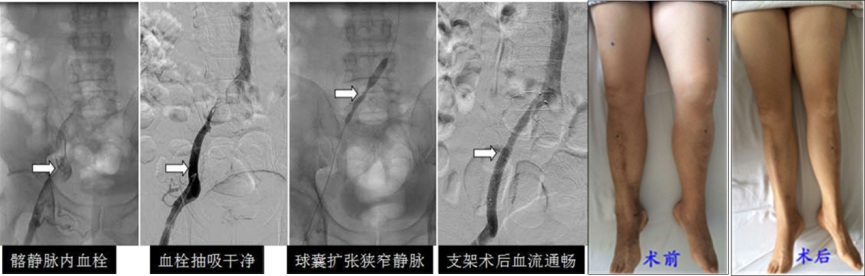

下肢深靜脈血栓的綜合介入治療

李某,女性,35歲,因左下肢脹痛4天入院,確診深靜脈血栓形成,同時(shí)髂靜脈受壓綜合征,經(jīng)血管腔內(nèi)綜合介入治療后脹痛消失。